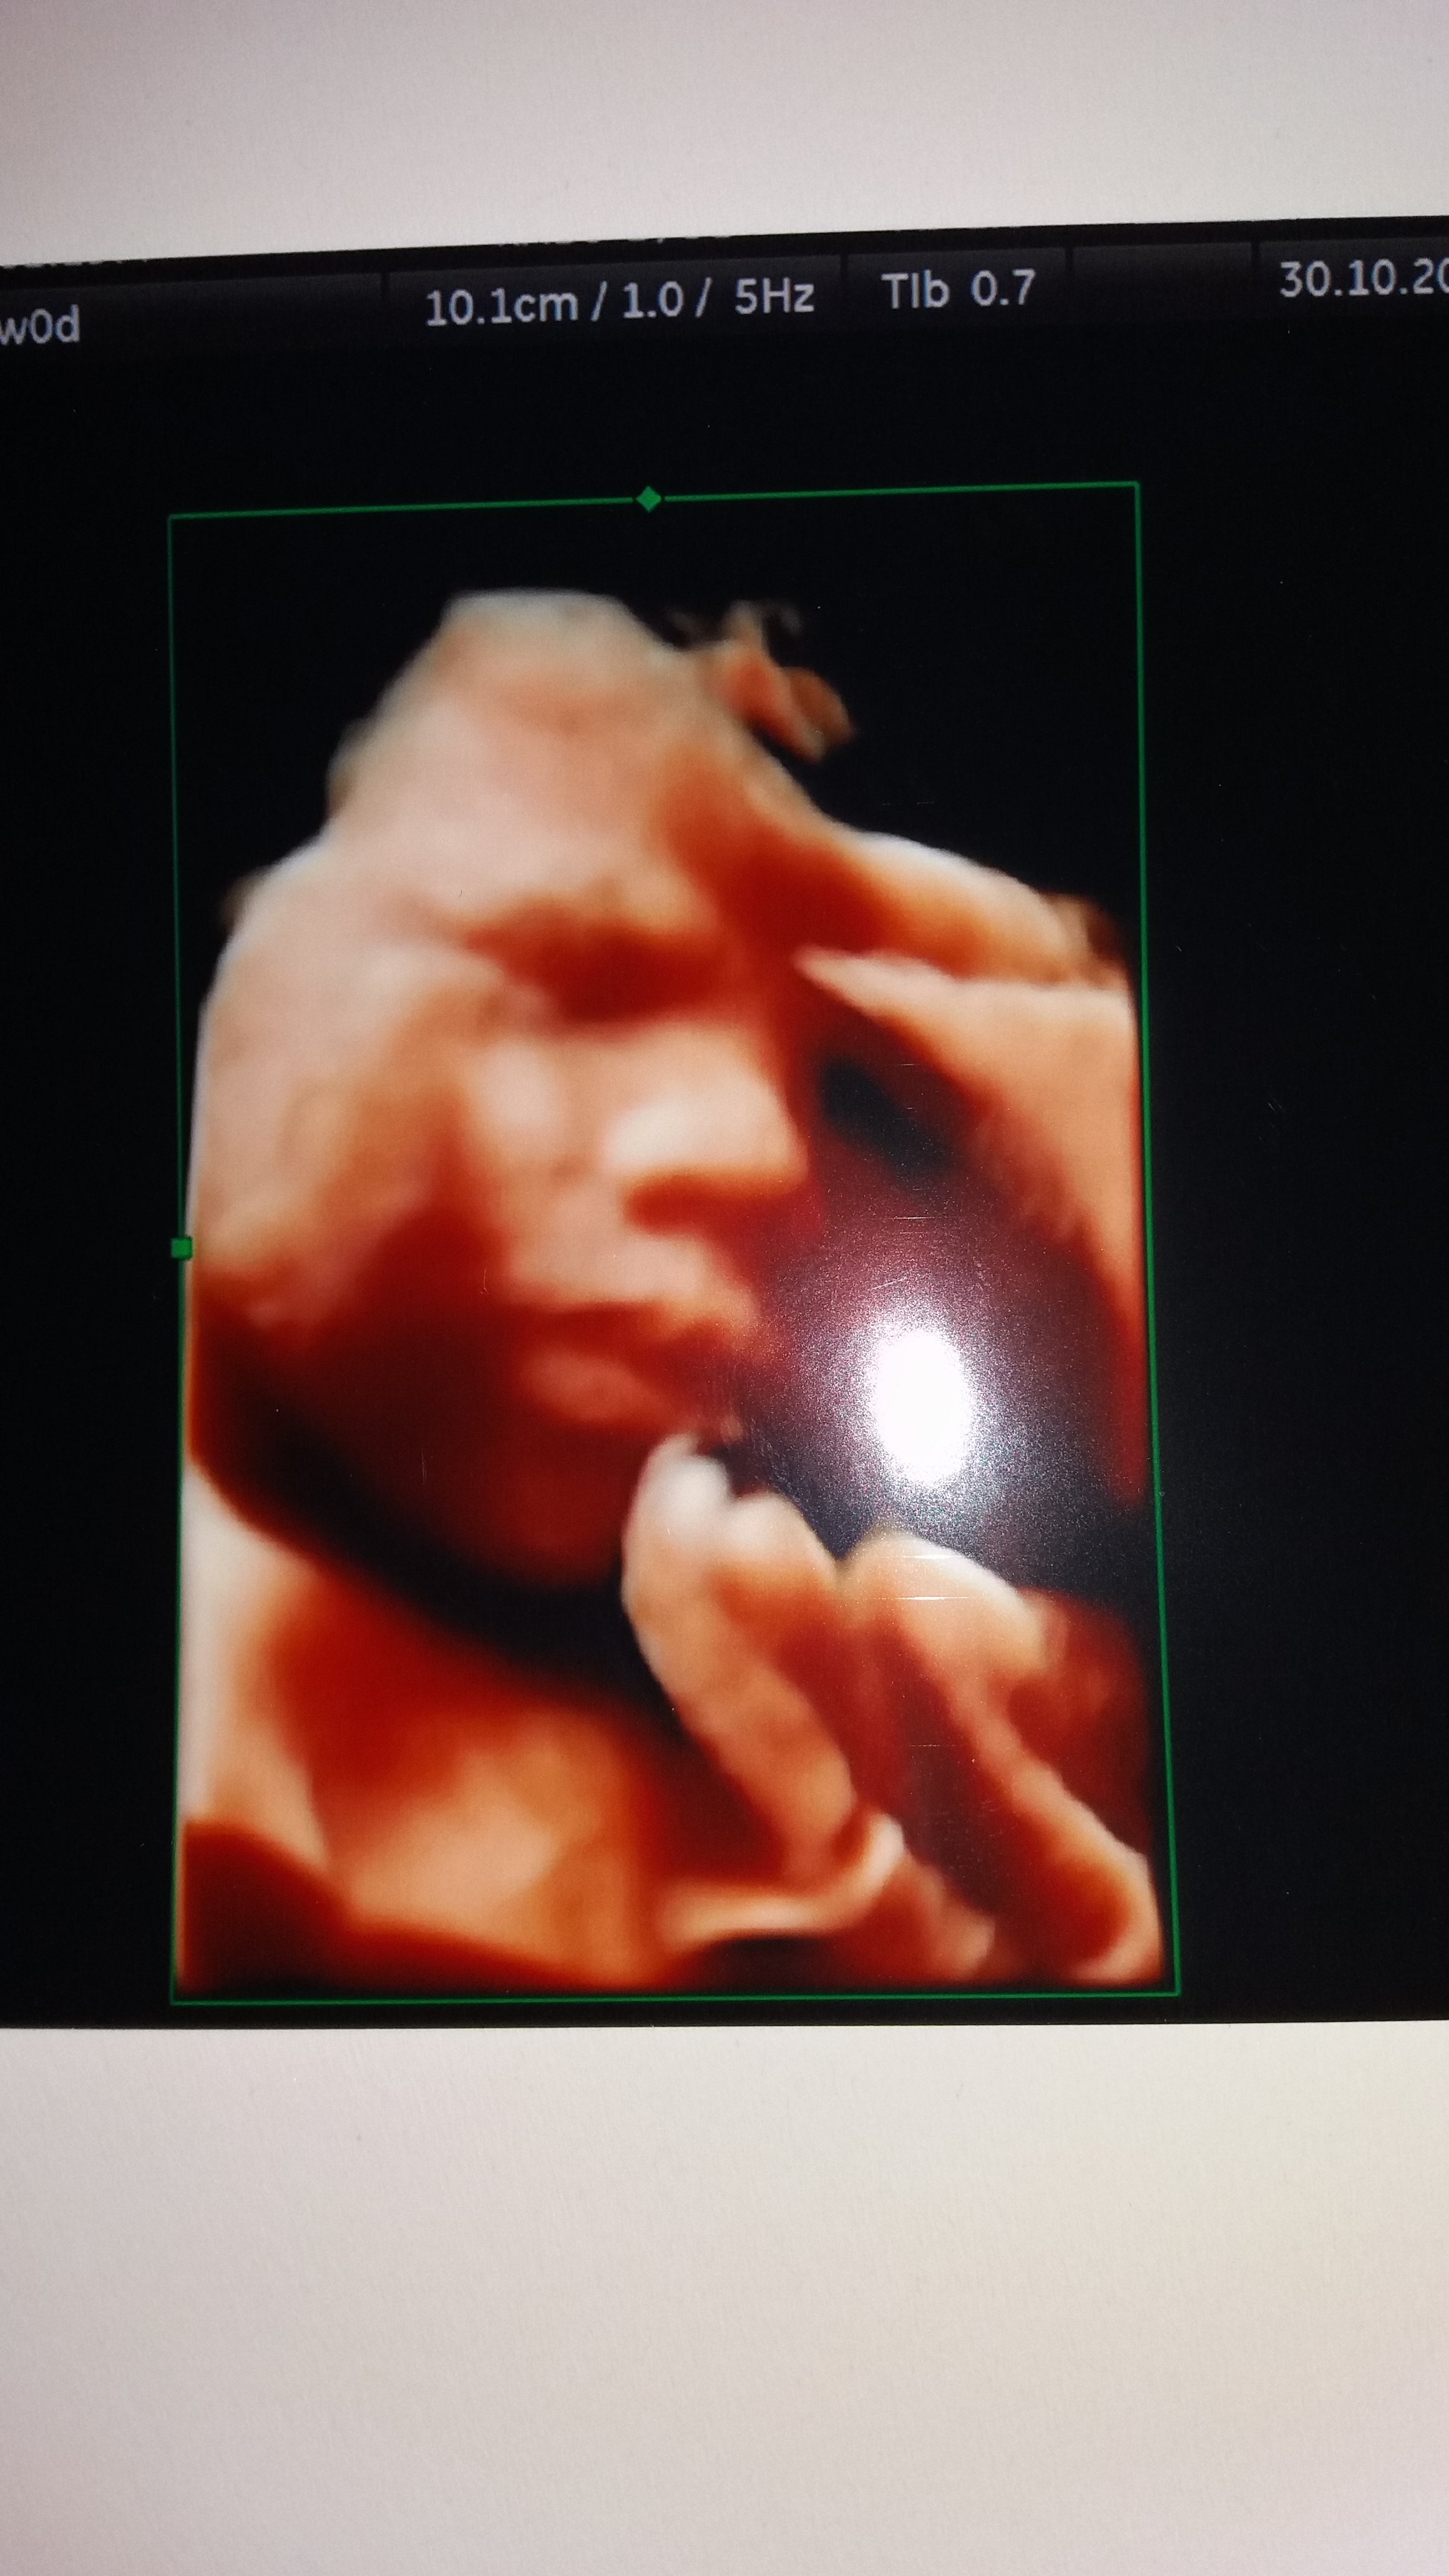

Ja właśnie leżę i mała nieźle daje mi popalić. Choć czasem boli to uwielbiam jej fikanie.A to nasze szczęście

Załączniki

• 20171031_072643.jpg

20171031_072643.jpg

848,6 KB · Wyświetleń: 102